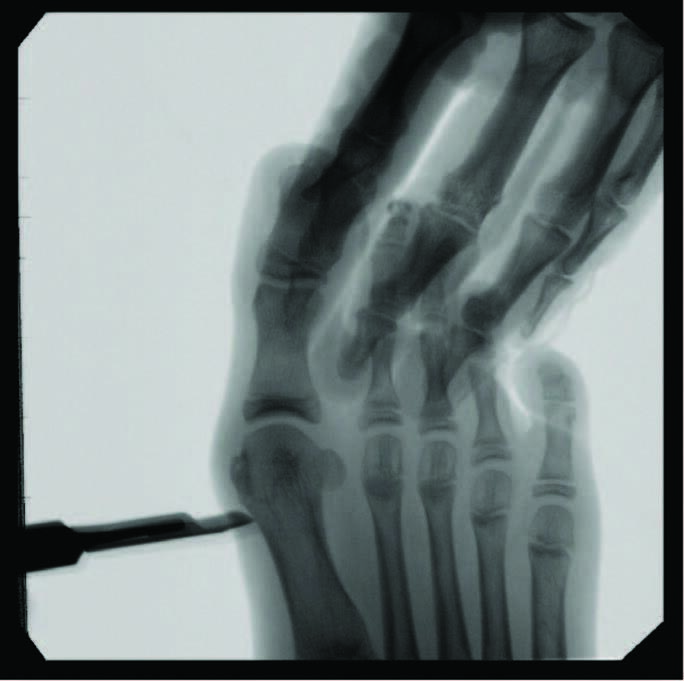

Minimally Invasive Approaches To Juvenile Hallux Abducto Valgus Deformity

Documentation of surgical correction of hallux valgus first occurred in the early 1800s, with the earliest reports of percutaneous correction in the 1940s. Podiatric physicians experienced surgical restrictions at this time, and MIS provided an avenue for circumvention. Complications arose due to a lack of supportive means, and these outcomes led to an abrupt return to open procedures. The 1960s provided power equipment development and intraoperative fluoroscopy, which significantly improved outcomes of both open and percutaneous procedures. With the arrival of these modern tools, surgeons began to revisit the utilization of percutaneous procedures towards the end of the millennia. A subcapital osteotomy technique reported by Bosch, and “Simple, Effective, Rapid, Inexpensive,” modified by Giannini in the early 2000s, implemented a modern look at MIS hallux valgus procedures.8,9 Most recently, a guide to the percutaneous bunionectomy written by Siddiqui in 2014, and MIS radiographic outcomes in 2016, provided another available tool to surgeons, which decreased the complication rates and expanded the confidence in utilization of MIS bunion correction universally.10

Open and percutaneous osseous procedures rely on physiologic principles of soft tissue and bone healing, where Davis’ and Wolff ’s laws each describe that tissue healing models along imposed demands, according to how they are mechanically stressed. In our experience, allowing patients to weight-bear immediately after surgery will encourage mechanotransduction through stress and load along the osteotomy site. The opposite will occur with a decrease in load and demand along the medial aspect of the first metatarsal, known as the “medial step,” which is just proximal to the osteotomy. Due to the lack of stimulus along the anatomic area, the bone will be less dense; therefore, in theory, it should remodel along the osteotomy site. We feel that one should still consider smoothing out the ‘medial step off ’ along the MIS osteotomy if a ledge is appreciable intraoperatively.

Although minimally invasive hallux valgus surgery is a more modern technique, especially for the pediatric population, it still relies, in my experience, on AO principles of fracture fixation, including anatomic reduction in the first intermetatarsal and hallux abductus angles, stable fixation, preservation of blood supply, and early active mobilization. I find the percutaneous approach allows the reduction of a wide range of mild to severe radiographic angles and preservation of blood supply. In a study of minimally invasive bunion procedures, surgeons achieved up to a 12.5 degree correction of the first intermetatarsal angle and reported a 5.3 percent reoperation rate. The study was from a surgeon’s first 94 MICA procedures, and the author challenged the previously reported steep learning curve, citing low complication rates and ease of reproducibility.13

Over the last decade, I, the senior author, have performed hundreds of bunion procedures through both traditional and minimally invasive approaches. My criteria for surgical candidacy for MIS procedures started in the high-risk wound population with multiple comorbidities, including patients with diabetes, human immunodeficiency virus (HIV), acquired immunodeficiency syndrome (AIDS), rheumatoid arthritis (RA), and transplant recipients. All of these populations of patients are at higher risk for surgical complications, such as infections and wound and bone healing delays. My outcomes and results in these patients were so remarkable that I then expanded my criteria to include healthier and higher-demand populations, including children and athletes. In my experience, this surgical approach can help address a complex deformity in the young population, decreases postoperative rehabilitation, improves function, and avoids disrupting a child’s open growth plate. All possible without leaving hardware behind.